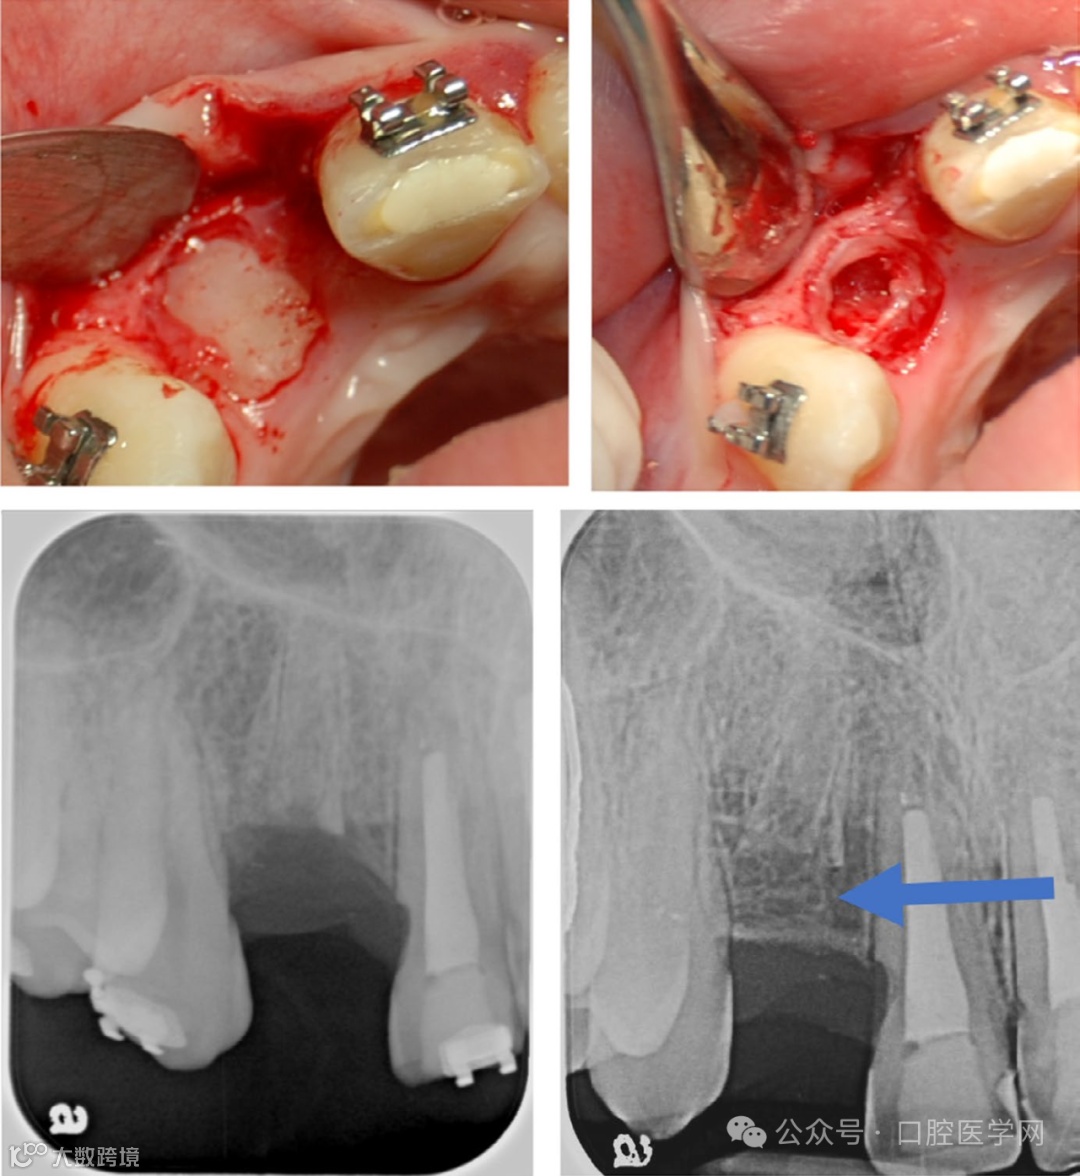

图3

进行冠切除术以保留骨质用于未来种植体植入。请注意随访放射影像中标记有箭头处(coronal to the root)的骨质生长情况。(图片由Yuli Berlin-Broner博士和Eyal Nuni博士提供)